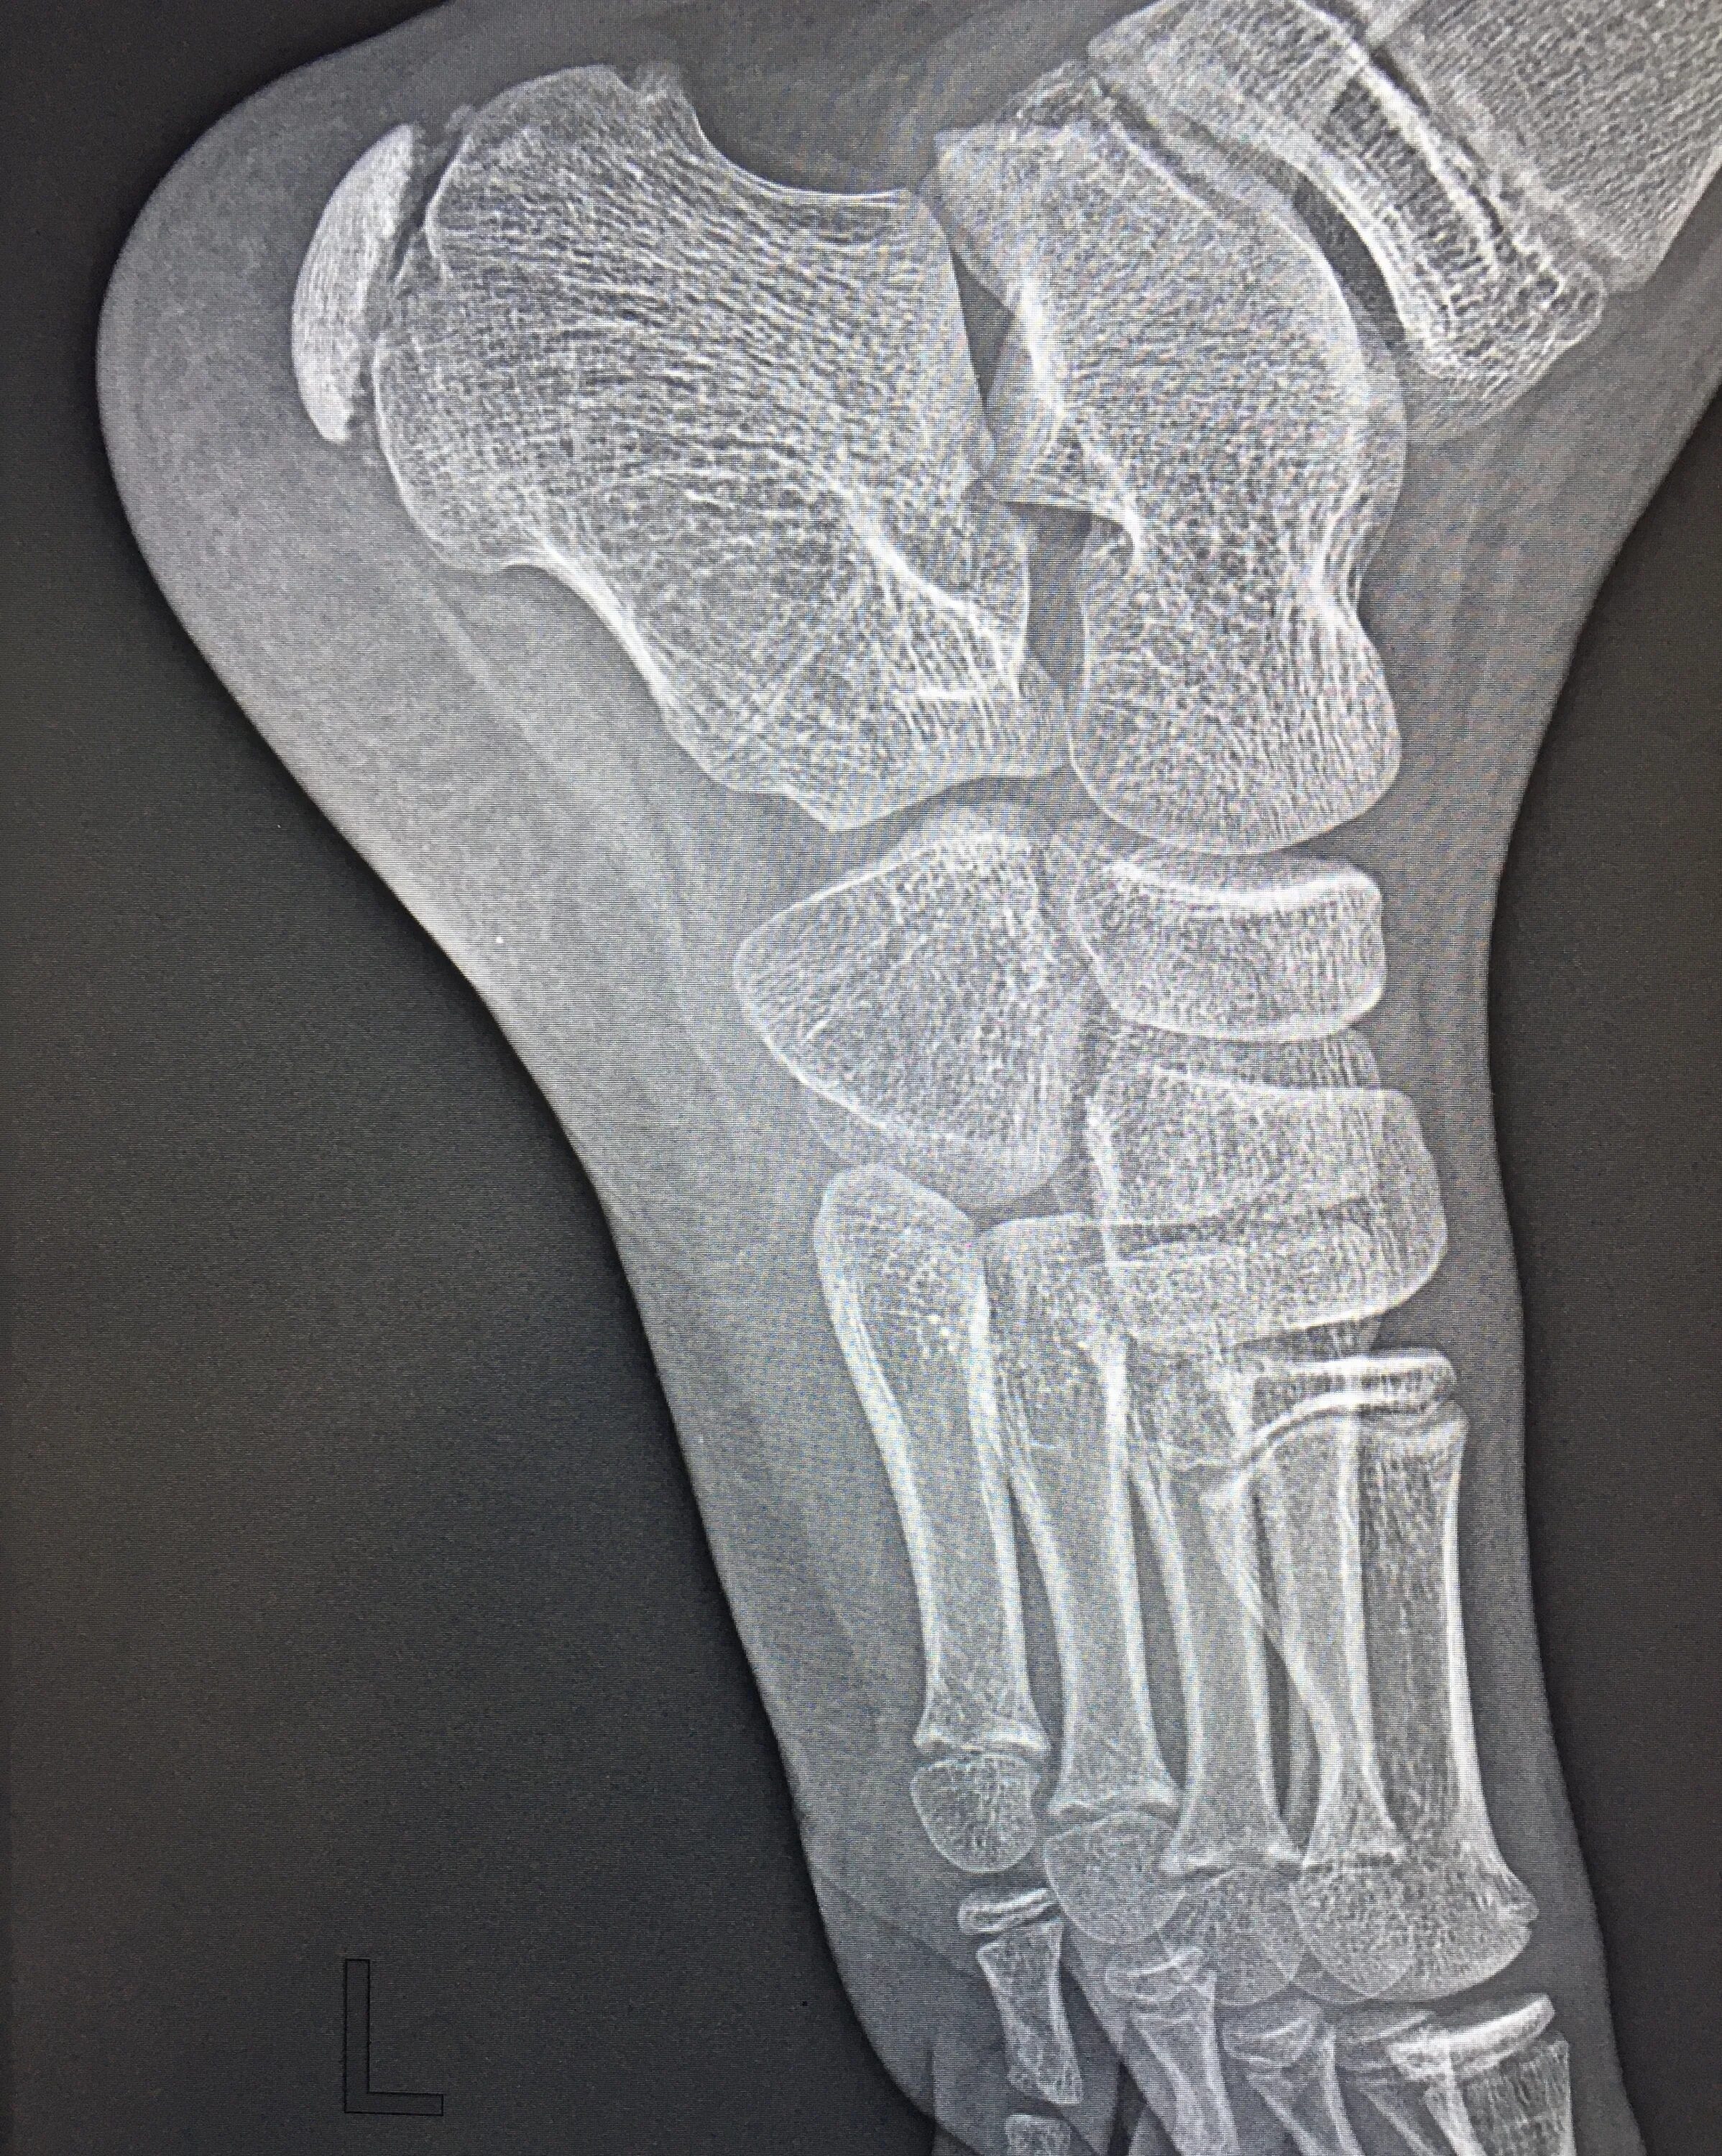

Болезнь шинца у детей код по мкб